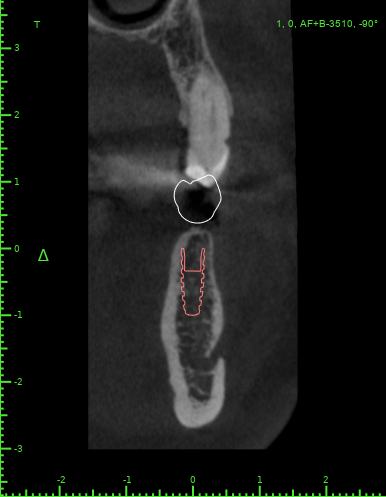

Женька Опубликовано 10 декабря, 2021 Автор Поделиться Опубликовано 10 декабря, 2021 @kamranchick чисто винтами? или нужно ортодонта подключить? Планируется вот так Ссылка на комментарий

АнтонТЛТ Опубликовано 10 декабря, 2021 Поделиться Опубликовано 10 декабря, 2021 А ортопед не хочет немного шлифануть этот зуб? Винты ставить из-за 1.5 мм, как-то жёстко) Планирование в каком софте? 2 Ссылка на комментарий

Женька Опубликовано 11 декабря, 2021 Автор Поделиться Опубликовано 11 декабря, 2021 @АнтонТЛТ blue sky plan Антон, я передам эти мысли ортопеду А подождите, я же скорее всего сам и буду это протезировать . И пожалуйста, объясните мне когда можно шлифовать, а когда это овер трит. Я же правильно понимаю, что немного шлифануть, это оставить его без покрытия коронкой? Ссылка на комментарий

АнтонТЛТ Опубликовано 11 декабря, 2021 Поделиться Опубликовано 11 декабря, 2021 В Блю скае есть ортодонтический модуль, можно элайнеры сделать и задвинуть немного этот зуб) Шлифовать в пределах эмали. Попросите техника отмоделировать зубы, будет понимание на сколько можно сошлифовать. Ссылка на комментарий